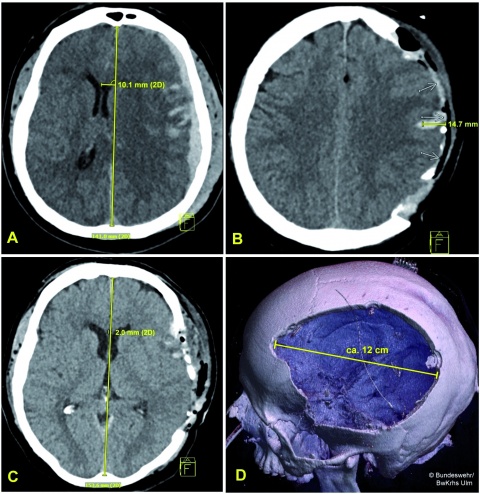

Craniales CT einer 56jährigen Patientin: (A) Präoperativ

Subduralhämatom und

traumatisches Hirnödem links mit

einer Mittellinienverlagerung von

ca 1cm -> vitale OP-Indikation;

(B) Postoperatives cCT nach

Entlastungskraniektomie und

Blutungsevakuation mit schwellungsbedingtem

Hirnprolaps von ca. 1,5cm; (C) Wiederherstellung der Mittellinienposition; (D)

postoperatives cCT mit Volume

Rendering zur Darstellung des

Kalottendefektes.